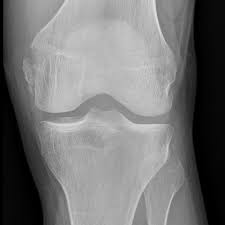

Medial Ligament Fifa Medical Platform

Medial Ligament Fifa Medical Platform from www.fifamedicalnetwork.com